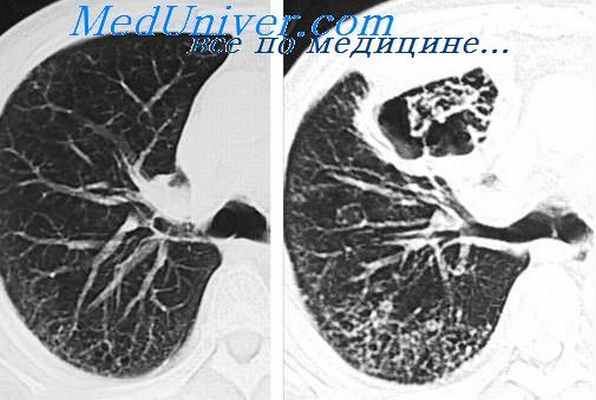

Здесь представлены компьютерно-томографические срезы на разных уровнях. Мы имеем возможность видеть просветы всех бронхов, оценить состояние их стенок и окружающей легочной паренхимы. Для того чтобы лучше оценить характер патологических изменений, возможно использование КТ высокого разрешения.

Очень хорошо дифференцируются утолщенные стенки, наличие содержимого в просвете бронхов (бронхиолоэктазы), состояние бронхиальной обструкции.